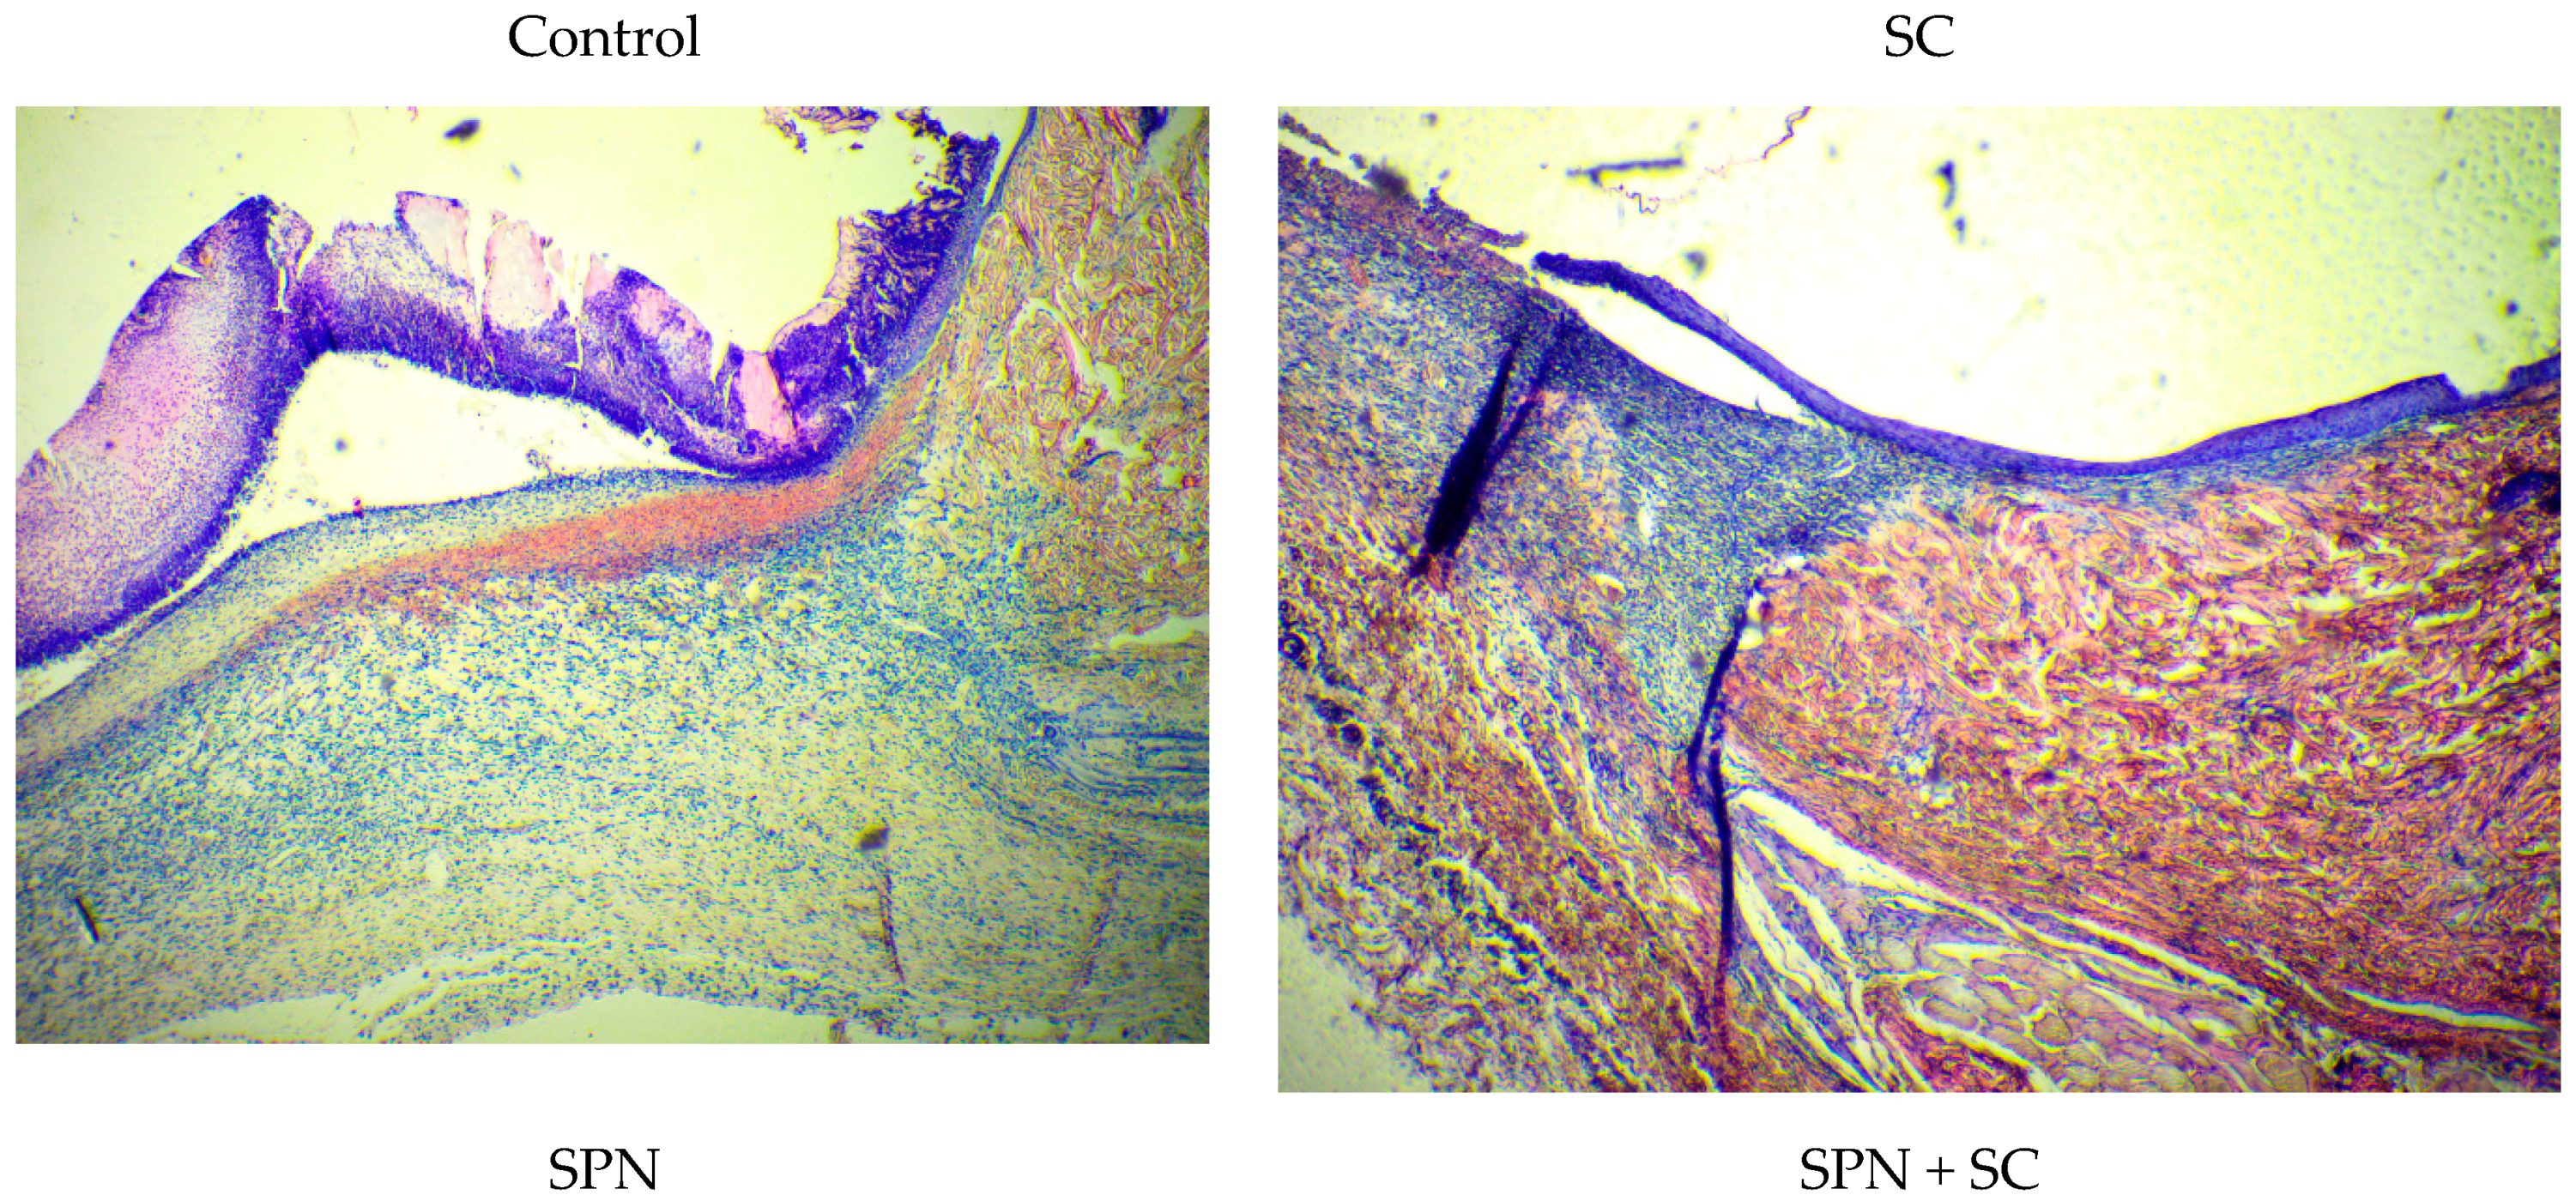

At the edges of the wounds, there were 1.2–1.4 times more resident cells than in the center of the wounds. Epithelialization correlated with this process. In all wounds, epithelialization was marginal. The greatest difference in the content of resident cells in the center and at the edges of wounds was in the control group, where epithelialization was the smallest. Thus, microscopy revealed that, in the edges of the wounds of the control group on day 7, signs of epidermal regeneration were the least pronounced. This was evidenced by the length of the newly formed epidermis (from the edges of the wound to the center), as well as the smallest number of layers of the epidermis in the control group. The best epithelialization (greater length and number of layers, including the superficial stratum corneum) was in the SPN and SPN + SC groups (Figure 11).

Figure 11.

Edge of wounds in different groups on day 7 (Hematoxylin–Eosin, magnification ×40).